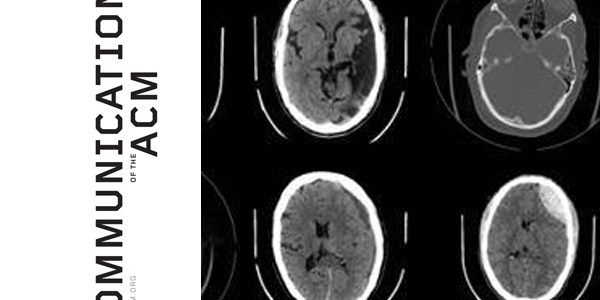

Artificial intelligence (AI) image analysis software has become more adept at diagnosing heart failure and various cancers than top-flight doctors, according to researchers at Case Western Reserve University in Cleveland, OH.